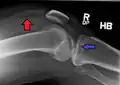

Lipohemarthrosis (presence of fat and blood from bone marrow in the joint space after an intraarticular fracture) seen on X-ray in a person with a subtle tibial plateau fracture -

Lipohemarthrosis due to a tibial plateau fracture -

Subtle tibial plateau fracture on an AP X ray of the knee -

A tibial plateau fracture seen on X-ray